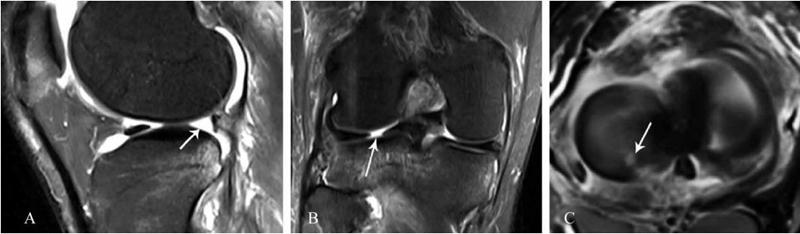

6、外侧半月板后根损伤

常是ACL损伤的合并伤。MRI上的表现有以下特征(图6): (1)冠状位,可见到外侧半月板后角靠近止点处有垂直线性缺损,也称为截断征或裂隙征;(2)矢状位,可见到外侧半月板后角缺失,也称为幽灵征或者空半月板征;(3)轴位,可见到在外侧半月板后根处高信号,也称为横向线性缺损,分离移位者更加明显,这对外侧半月板后根损伤的诊断有非常重要的作用,但往往被忽视。

图6 外侧半月板后根损伤的MRI影像

A. 矢状位外侧半月板后角缺失(幽灵征);B. 冠状位外侧半月板后角靠近止点处出现截断征;C. 轴位外侧半月板后根处有横向线性缺损